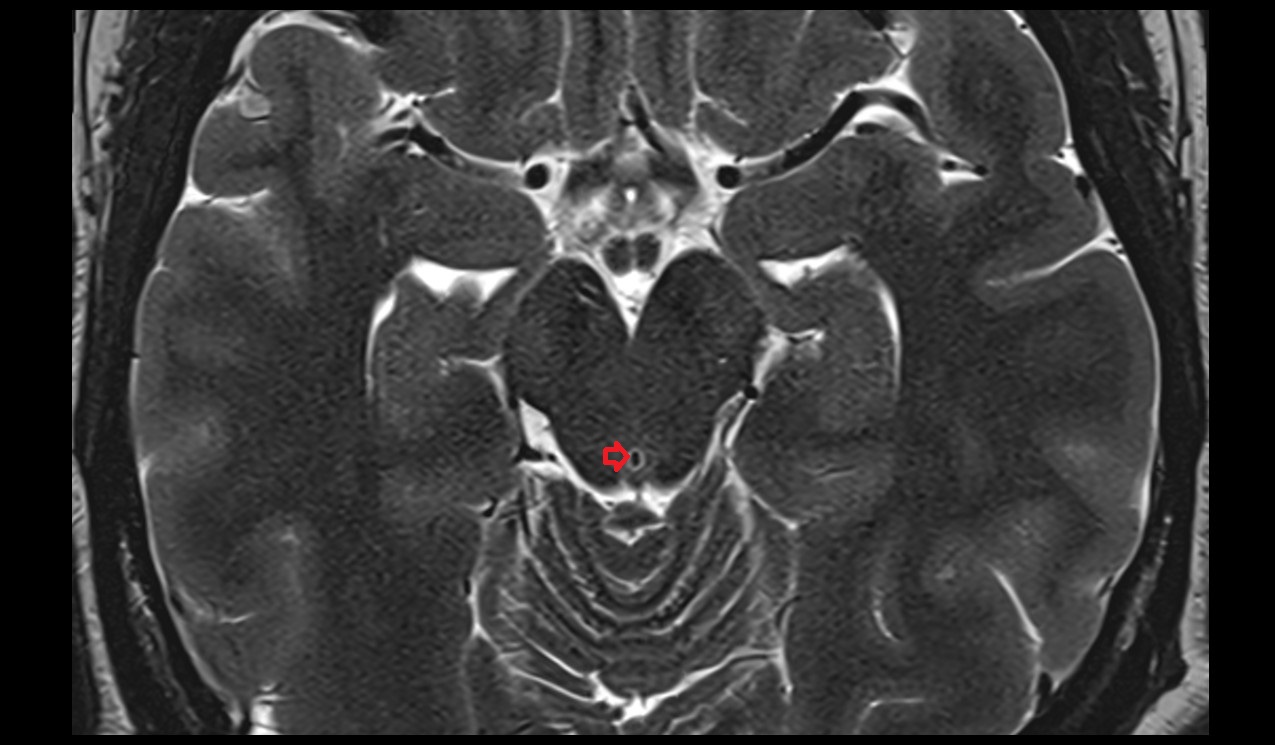

- Median aperture of fourth ventricle (foramen of Magendie)

- Lateral aperture of fourth ventricle (foramen of Luschka)